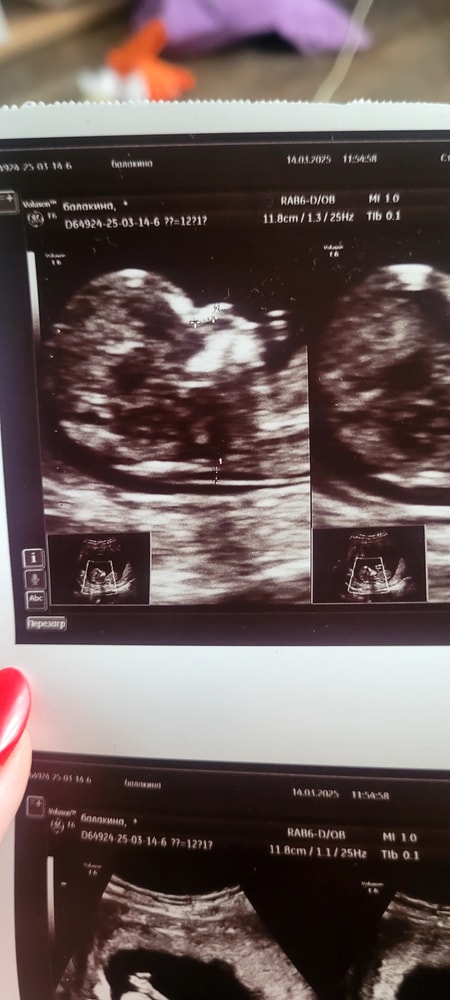

1 скрининг пройден

УЗИ, КТГ, доплерТак переживала перед скринингом, но все слава Богу хорошо, малыш растёт, развивается, по сроку уже опережает на 5 дней. В заключении все хорошо, что очень порадовало. Малыш на узи махал ручкой, устраивал джигу-дрыгу😁.

Фото моего крохи, профиль